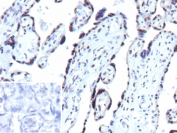

Immunohistochemical analysis of CDKN1B in FFPE human placenta using a CDKN1B/p27Kip1 antibody (clone r1B4). Distinct nuclear staining is observed in placental cells, consistent with Cyclin-dependent kinase inhibitor 1B localization. Staining of formalin-fixed tissues requires heating tissue sections in 10 mM Tris with 1 mM EDTA, pH 9.0, for 45 minutes at 95 C followed by cooling at room temperature for 20 minutes. Inset shows a negative control section processed in parallel using PBS in place of the primary antibody, demonstrating minimal background staining.